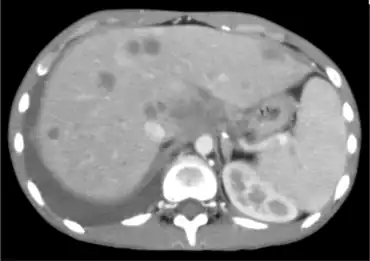

| Image with disseminated coccidioidomycosis | |

Disseminated coccidioidomycosis is a systemic infection with Coccidioides immitis, in which 15-20% of people develop skin lesions.[1]: 315